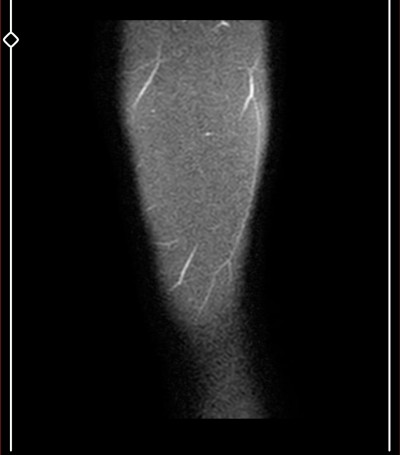

Kızlar çok önemli benim için aşırı şekilde dizlerim ağrıyor böyle çıktı

Mr sonucunu yazılı olarak birkaç güne alabilirsin tatlım biz bilemeyebiliriz sonuçta aramızda ortopedisyen yok  eşimdede sağlam bacakta tümör çıktı  3 cmlik o yüzden raporun çıkmasını bekle bence

Burada ortopedi hekimi yada radyoloji uzmanı yoksa bu görüntüleri kimse yorumlayamaz.Doktora sorulacak sorular bunlar